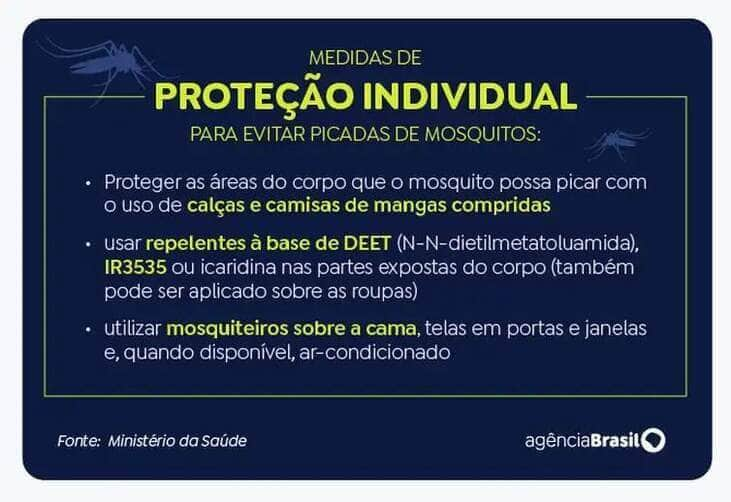

O controle dos criadouros de Aedes aegypti, as barreiras mecânicas para evitar que o mosquito entre nas residências, como telas em portas e janelas, o uso de inseticidas, de roupas apropriadas e de repelentes estão entre as recomendações para evitar a contaminação. O uso de inseticidas por vaporização ambiental, também chamada de nebulização espacial ou fumacê, ou domiciliar, também está entre as medidas recomendadas.

Segundo a Febrasgo, as gestantes devem priorizar o uso de repelentes aprovados pela Agência Nacional de Vigilância Sanitária (Anvisa), como picaridina, icaridina, N,N-dietil-meta-toluamida (DEET), IR 3535 ou EBAAP.

Medidas de proteção individual para evitar picadas de mosquitos. Foto: Arte/EBC